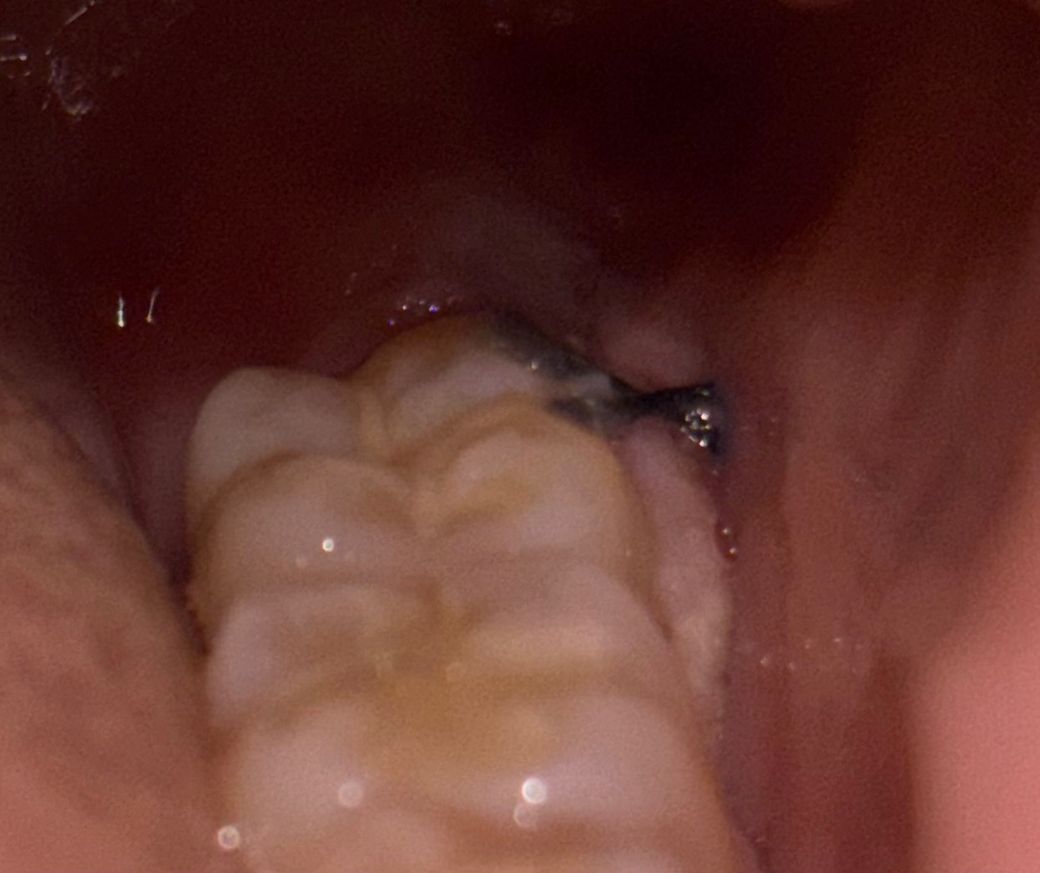

사랑니 발치 후 잇몸이 하얗게 변했어요

3일차에 음식물찌꺼기처럼 어금니와 잇몸 틈새에 흰색덩어리?가 있길래 소독한 면봉으로 살살 떼어냈더니 피가 나더라구요..?ㅠㅠ 그래서 그 뒤로는 거의 건들지 않고 방치했는데, 5일차인 오늘 아침에 봤을때보다 지금 정체모를 흰색덩어리?로 어금니와 잇몸 틈새 대부분이 덮였어요ㅠㅠ 도대체 정체가 무엇인가요?? 뜯어도 되는건가요…?ㅠㅠ 저번처럼 피날까봐 무서워요…

(생각해보니 오늘 아침에 일어났을때부터 실밥도 어제보다 풀린것같이? 되어있었고, 붓기도 갑자기 다시 생겼어요ㅠ)

• 1번 째 사진